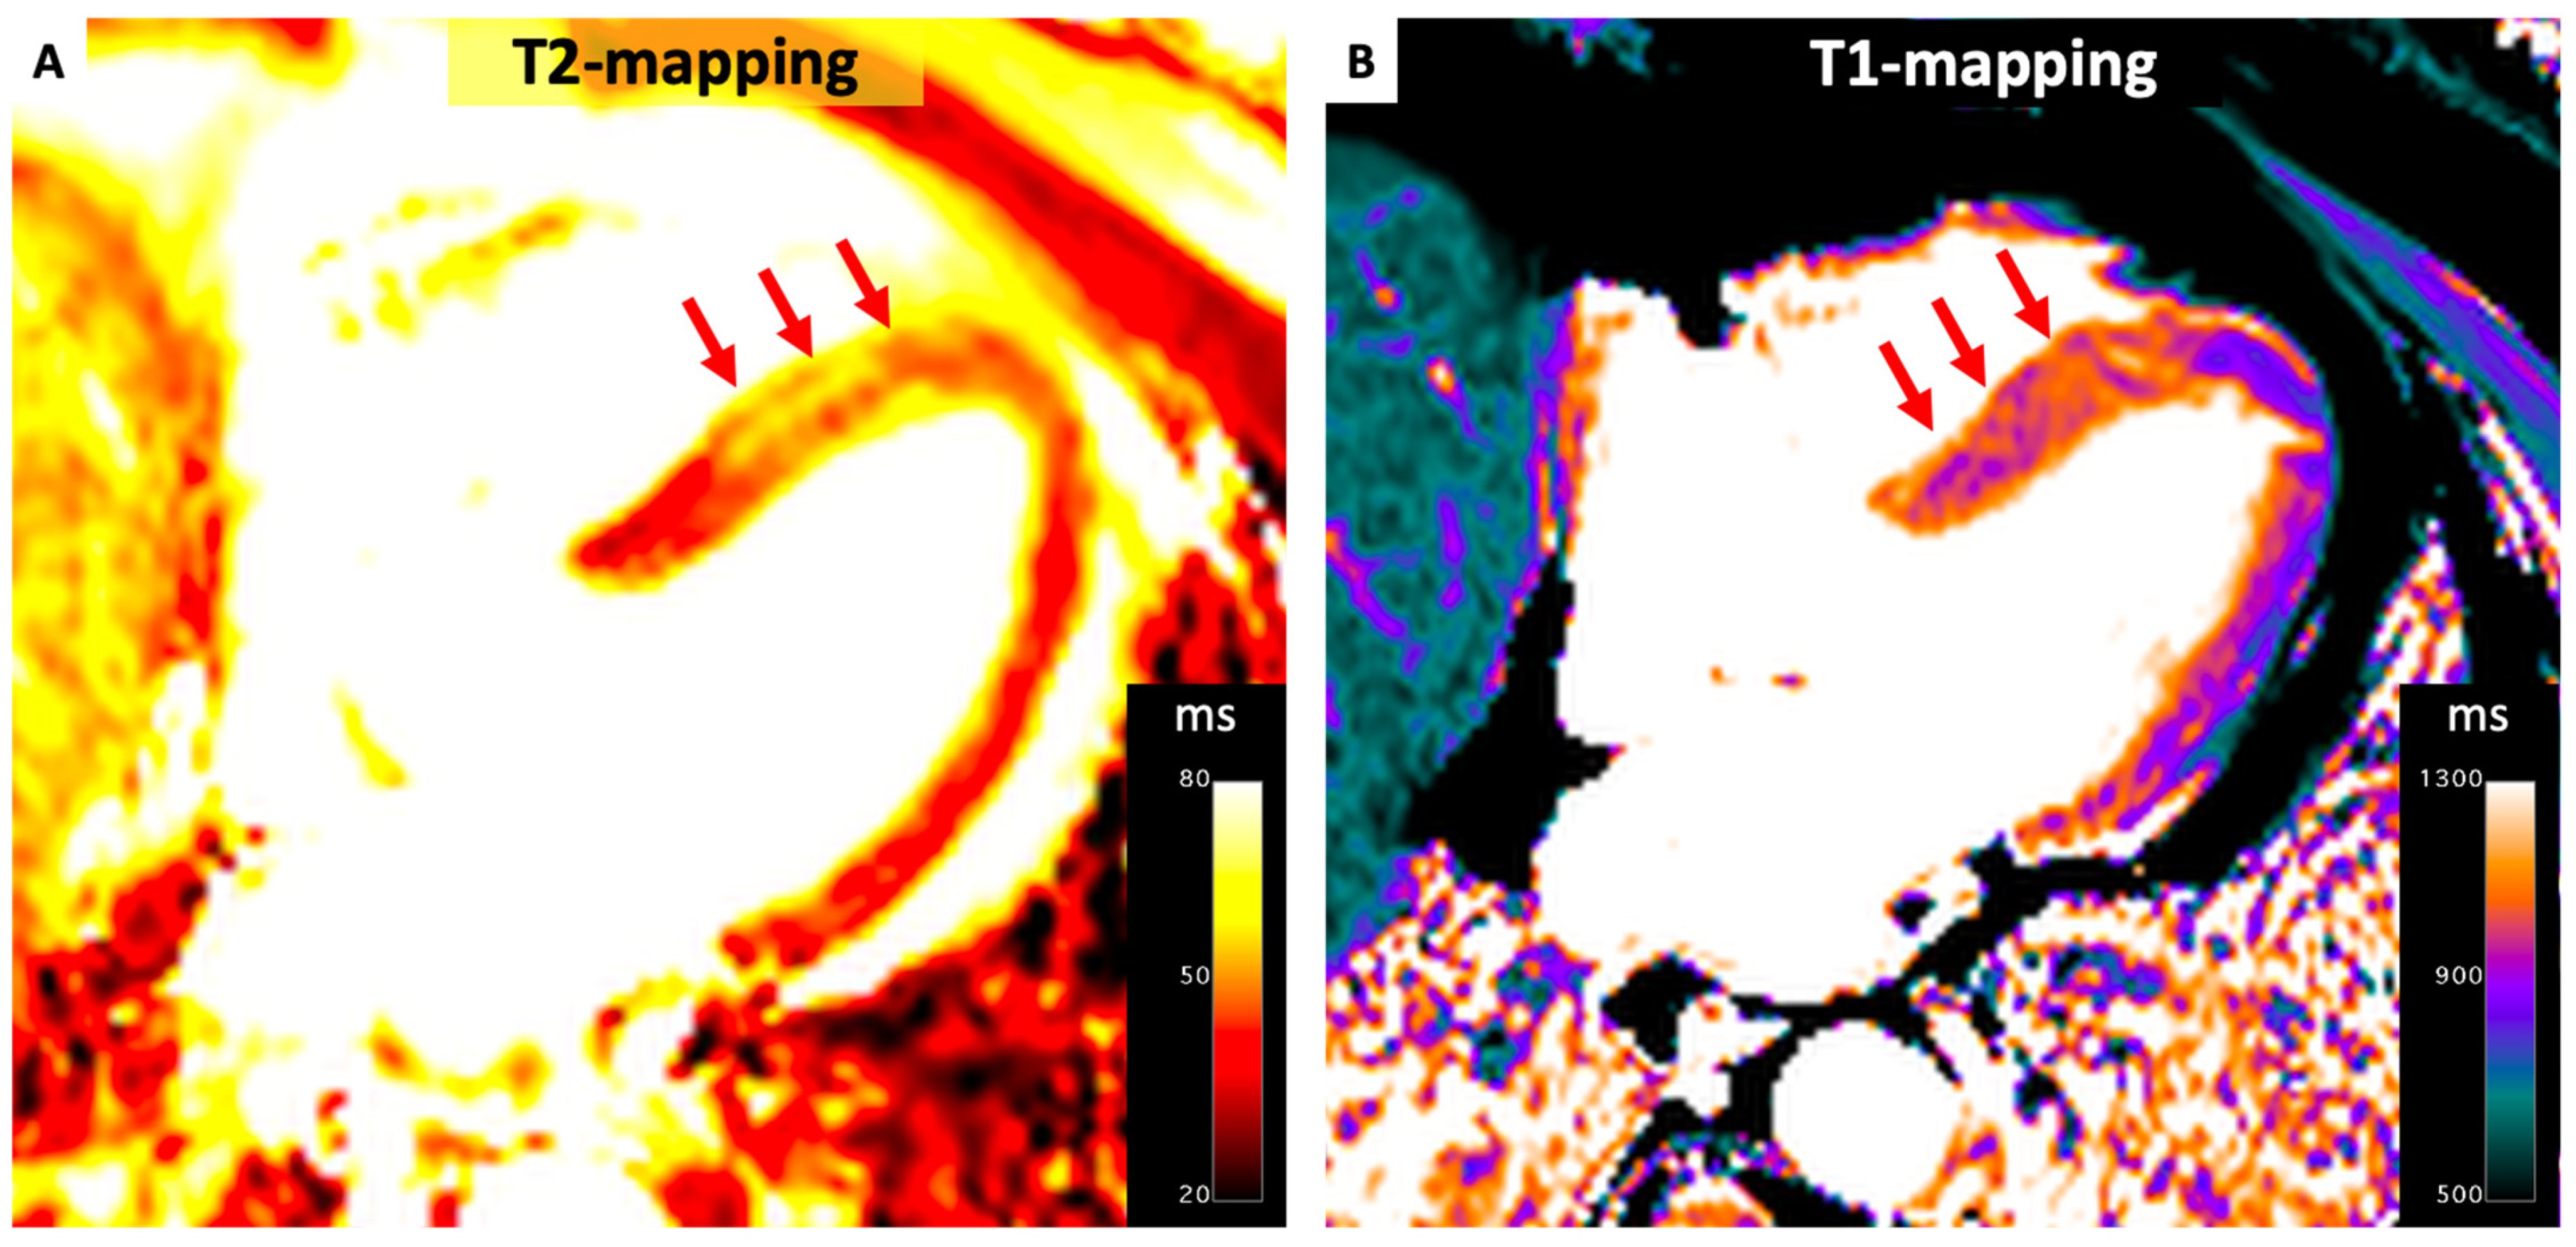

4.1. Ischemic Heart Disease